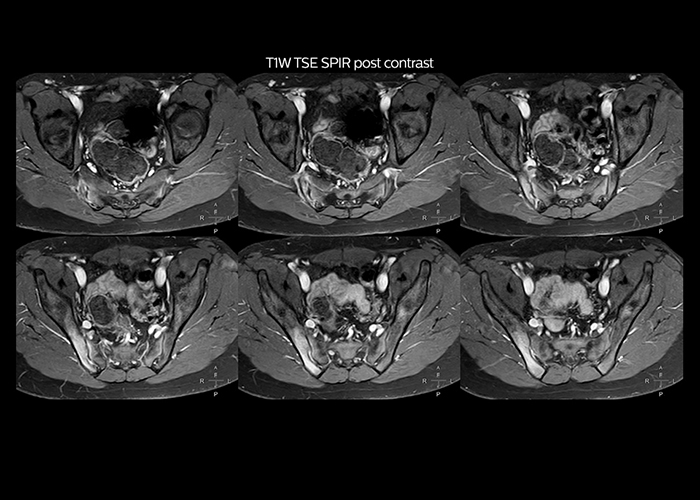

“On average, we scan about 80 patients per day, but on some days we scan well over 100 patients. The scanner is in use 7 days per week, operated 20 hours per day on week days and 8 hours per day in the weekend,” Mr. Tuna says. “To avoid coil changes we plan examinations of similar anatomies back to back, such as head and spine. Multiva helps us here a lot because coils don’t need to be changed frequently. Moreover, thanks to parallel imaging technology and 16-channel HeadSpineTorso and 8-channel MSK coils we are able to achieve excellent image quality. In this way Multiva helped us to increase both image quality and productivity.” “Neurological cases, such as brain and spine imaging, represent the largest share in our MR scanning, followed by musculoskeletal cases. In general, we use simple and basic imaging protocols. But occasionally, we use advanced techniques for problematic cases if necessary.